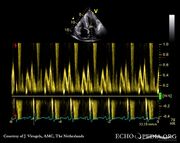

| 16:08, 11 March 2009 | MM0005.jpg (file) |  |

151 KB | Secretariat | 1 | |